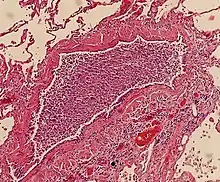

On gross pathology there are typically multiple foci of consolidation present in the basal lobes of the human lung, often bilateral. These lesions are 2–4 cm in diameter, grey-yellow, dry, often centered on a bronchiole, poorly delimited, and with the tendency to confluence, especially in children.

Light microscopy typically shows neutrophils in bronchi, bronchioles and adjacent alveolar spaces.[2]